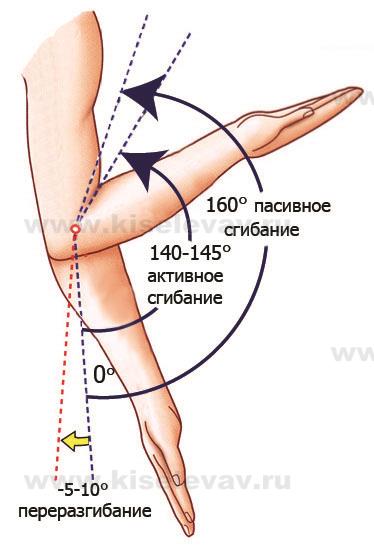

Диаграммы и схемы движения в суставах человека